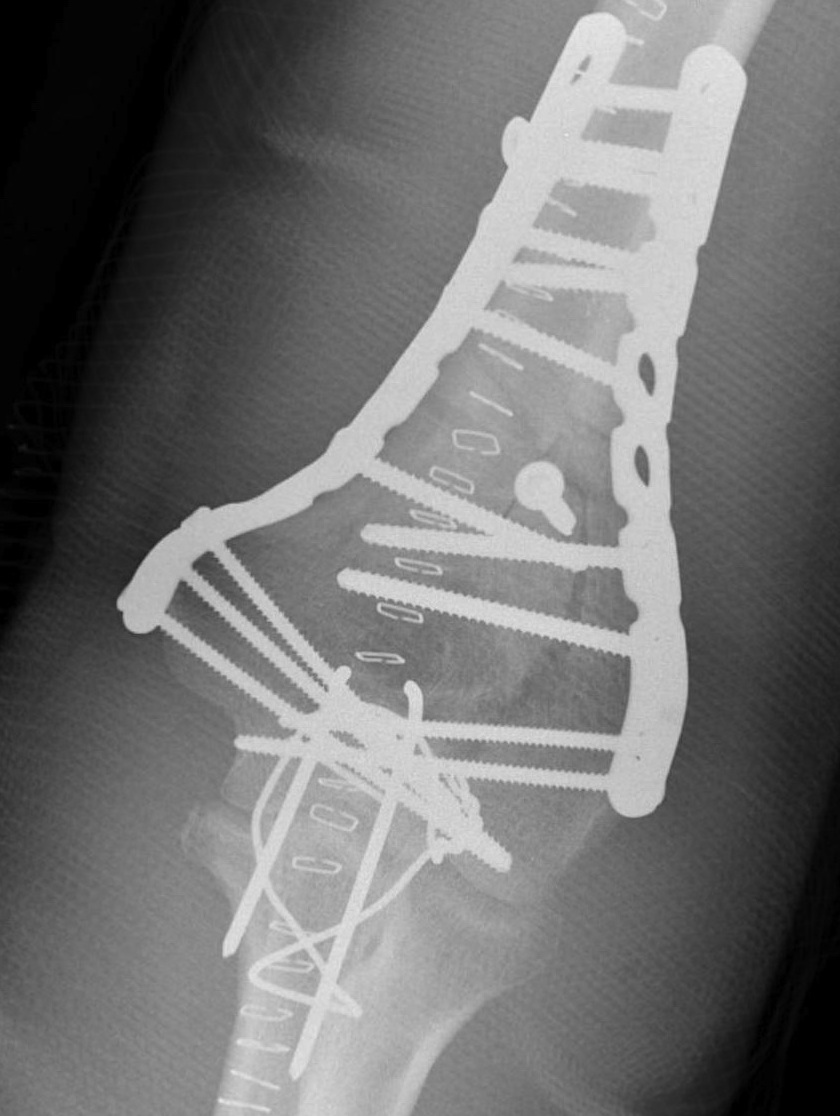

Fixation techniques

Options

Precontoured anatomical plates

Parallel plates v perpendicular plates

Parallel v perpendicular plates

Parallel plates - medial plate on medial column and lateral plate on lateral column

Perpendicular plates - plates at 90 degrees, with lateral plate posterior

- biomechanical superiority of parallel plates versus perpendicular plates

- systematic review of 83 studies and 2362 patients

- parallel plating lower incidence of revision for fixation failure (1% v 6%)

- perpendicular plating reduced overall complication (45% v 54%)

- these complications included lower incidence neuropathy, wound dehiscence, and implant prominence